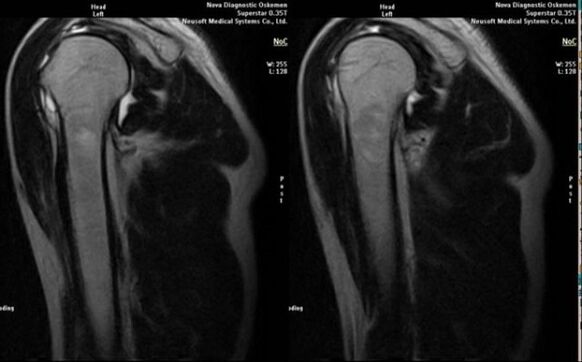

- magnetic resonance and computed tomography;

Signs indicating the development of arthrosis directly include the appearance of a significant narrowing of the joint space, sclerosis of subcartilaginous structures, thinning of the chondrocyte layer itself, the appearance of osteophytes and the deposition of salt crystals in the intra-articular fluid.